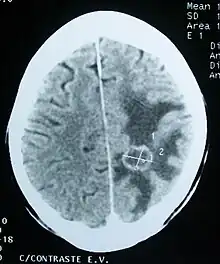

Imaging

CT scan of a brain tumor, with its diameters marked as an X. There is hypoattenuating (dark) peritumoral edema in the surrounding white matter, with a "finger-like" spread.

Medical imaging plays a central role in the diagnosis of brain tumors. Early imaging methods – invasive and sometimes dangerous – such as pneumoencephalography and cerebral angiography have been abandoned in favor of non-invasive, high-resolution techniques, especially magnetic resonance imaging (MRI) and computed tomography (CT) scans,[39] though MRI is typically the reference standard used.[42] Neoplasms will often show as differently colored masses (also referred to as processes) in CT or MRI results.